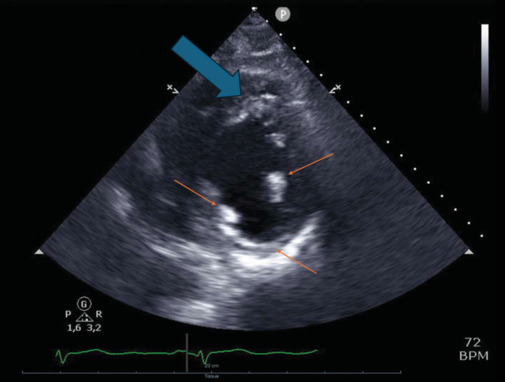

Cardiac sarcoidosis is an insidious condition with a highly variable clinical presentation that often mimics other diseases. Its diagnosis is particularly challenging, requiring a high index of suspicion and a comprehensive approach. Multimodality imaging plays a critical role in differentiating it from other conditions. We present a patient with cardiac sarcoidosis who also had concomitant coronary artery disease and colon cancer. The optimal therapeutic strategy for cardiac sarcoidosis remains uncertain. However, late gadolinium enhancement, a robust predictor of arrhythmic risk is crucial in guiding treatment decisions. This case report illustrates the risk of oversimplifying complex clinical scenarios by attributing signs and symptoms to a single disease, particularly in young, otherwise apparently healthy individuals. In such cases, clinicians must include rare diseases in their differential diagnosis.